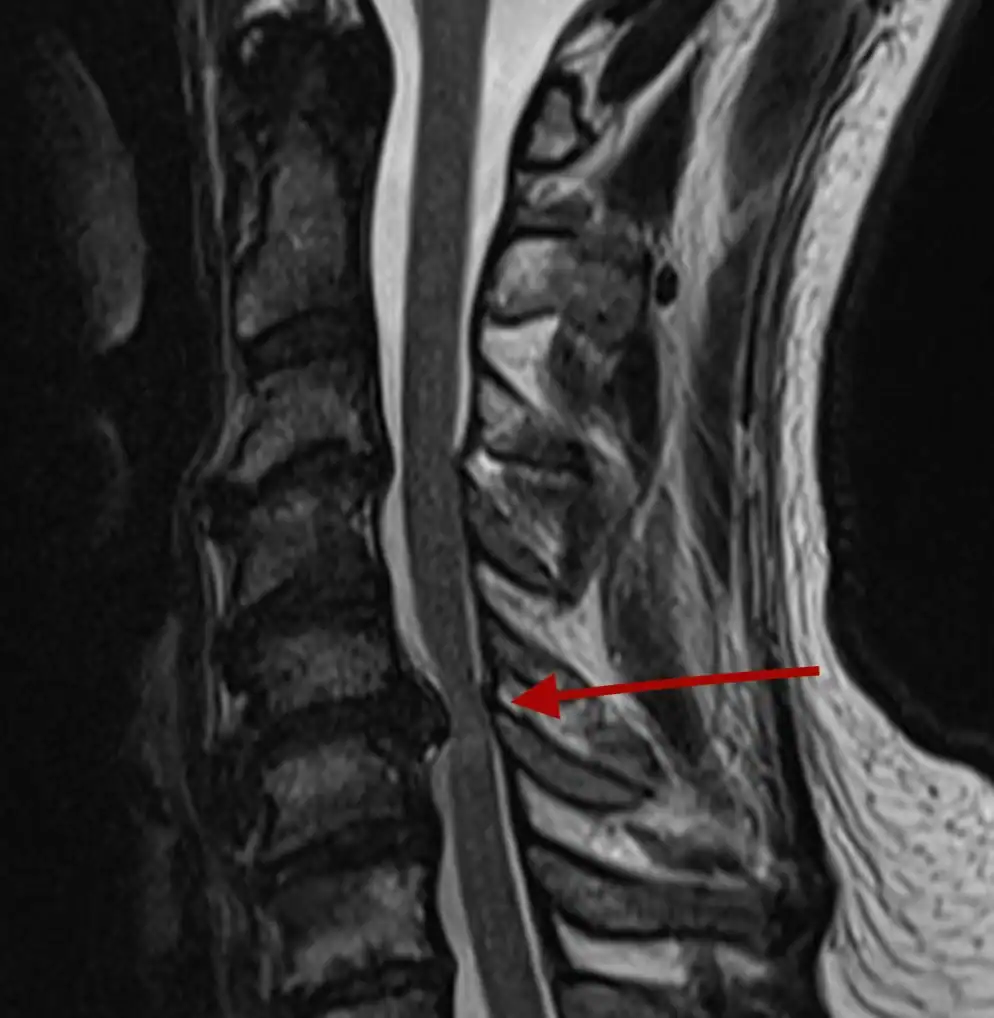

Wynik rezonansu: „dyskopatia lędźwiowa”. Dla wielu osób to moment niepokoju. W tym artykule wyjaśniamy, co naprawdę oznacza ta diagnoza, kiedy powoduje ból, czy zawsze wymaga operacji i jaką rolę odgrywa odpowiednio prowadzona fizjoterapia.